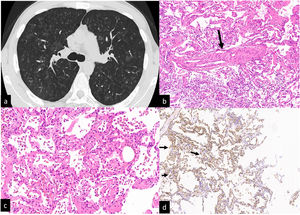

A pulmonary CT pulmonary angiogram ruled out pulmonary embolism, documented the presence of multiple, diffuse, centrilobular ground-glass nodules, a few intraparenchymal cysts, and an increased caliber of the main trunk of the pulmonary artery (Fig. 1 a). Areas of air trapping were not present even in the expiratory phase. A hypothesis of PCH was suggested by our thoracic Radiologist with hypersensitivity pneumonitis with pulmonary hypertension as a second, less probable, hypothesis.

CT scan without contrast. Multiple ill-defined ground glass centrilobular nodules distributed to both lungs. No mosaic attenuation related to air trapping is visible (a). Transbronchial cryiobiopsy:an interlobular vein with the lumen partially obstructed by fibrous tissue (b, arrow). Interstitial thickening is due to hyperplastic/dilated capillary-like vessels (arranged in superimposed rows). Hemosiderin-laden macrophages in the alveolar spaces (c). Alveolar capillaries marked by CD31 monoclonal antibodies are arranged in superimposed rows (d, arrows).

After the procedure, the patient developed a pneumothorax resolved in two days after the positioning of a chest tube. The four samples had a total area (measured under the microscope) of 189.11 mm2. Visceral pleura was present only in one sample. Histopathologic findings were: pulmonary veins in the interlobular septa with a lumen partly obliterated by fibrous tissue; vaguely nodular areas showing thickening of the interalveolar septa by the presence of dilated capillary-like vessels superimposed in more than one row. The surrounding alveolar spaces contained hemosiderin laden macrophages. The endothelial cells of the dilated capillaries were marked by anti CD31 monoclonal antibodies (Fig 1b-2d). A diagnosis of PCH/VOD was later confirmed. An off-label treatment with Imatinib was started and the patient was referred for lung transplantation.